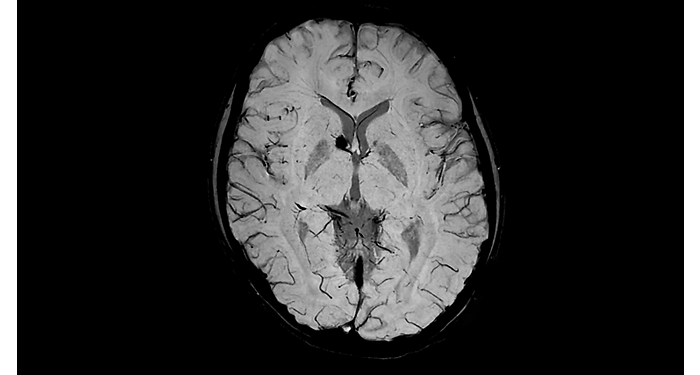

Hospital Eramse, Bélgica

Imágenes de la IRM de campos oscuros de un paciente con VIH con vasculitis cerebral

Las imágenes de campos oscuros ayudaron a sugerir el diagnóstico y elegir el tratamiento.